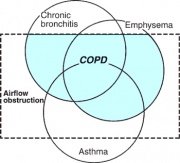

| 08:28, 5 במרץ 2015 | COPD1.jpg (קובץ) |  |

40 קילו־בייטים | Motyk | שוחזר לגרסה מ־11:21, 16 ביולי 2012 | 2 |